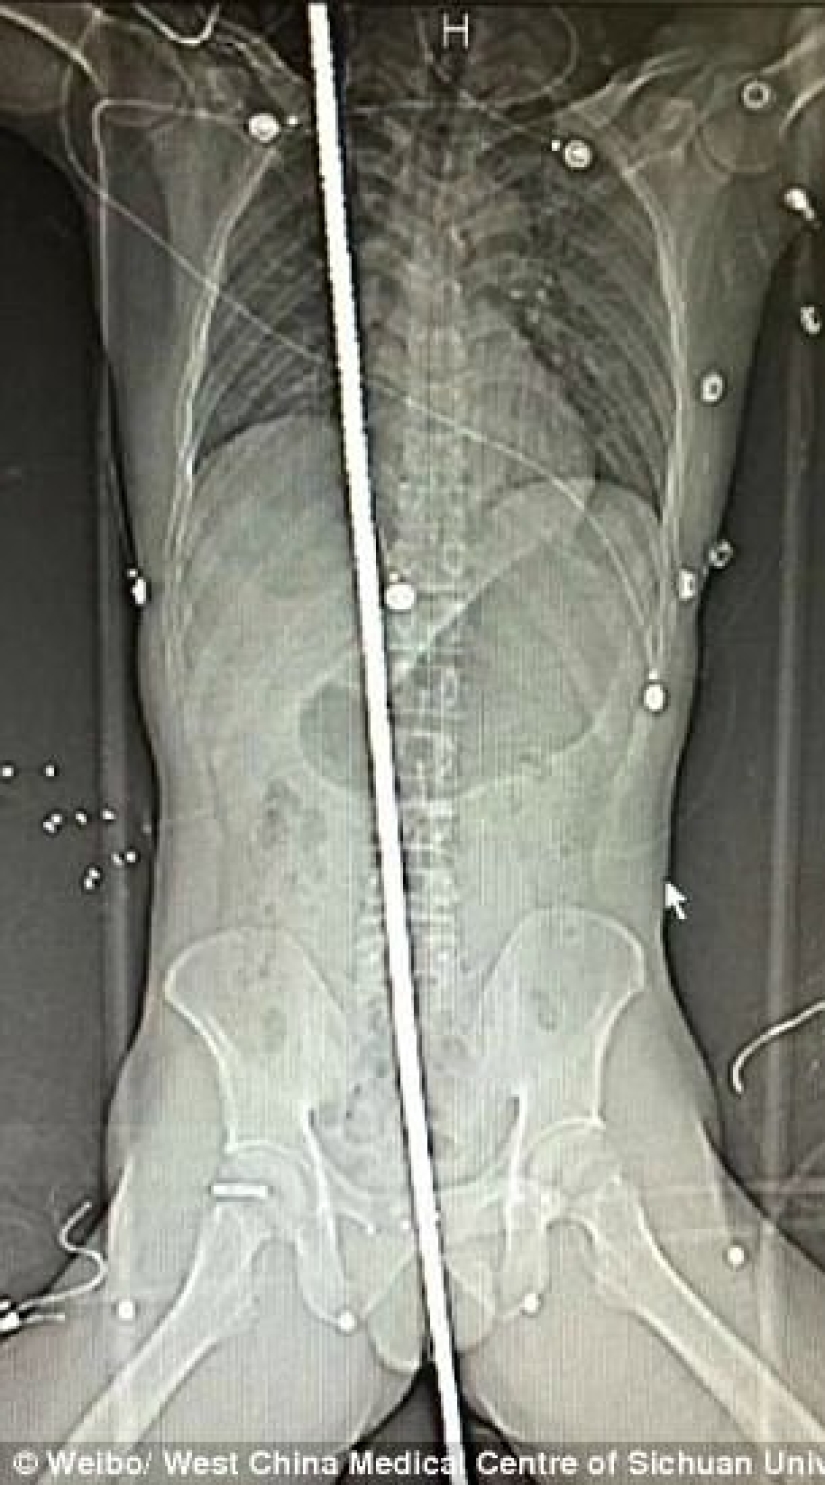

On September 18, a 37-year-old man was struck by lightning at a construction site in Chengdu, southwest China. He fell and landed right on the protruding rebar. A two-meter metal beam passed through the entire body. The victim was urgently hospitalized.

The X-ray showed that the rod pierced the diaphragm and passed through the right side of the pericardial sac.